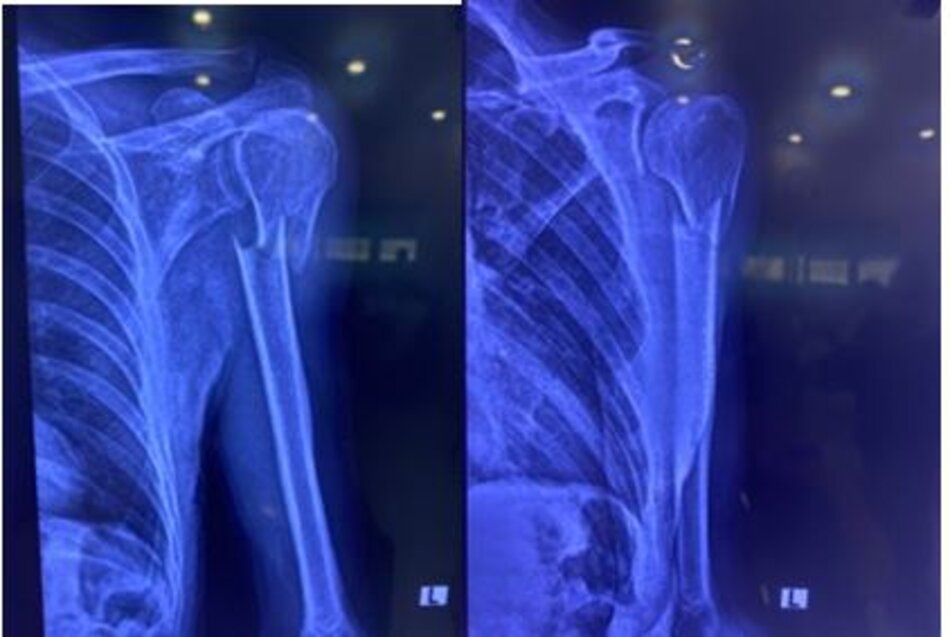

Phẫu thuật KHX cánh tay ít xâm lấn dưới màn tăng sáng

Kết hợp xương nẹp vít ít xâm lấn với đường mổ nhỏ điều trị gãy đầu trên xương cánh tay

X-quang trước phẫu thuật trong tư thế thẳng và nghiêng

X-quang sau mổ và đường mổ ít xâm lấn với 2 đường rạch nhỏ